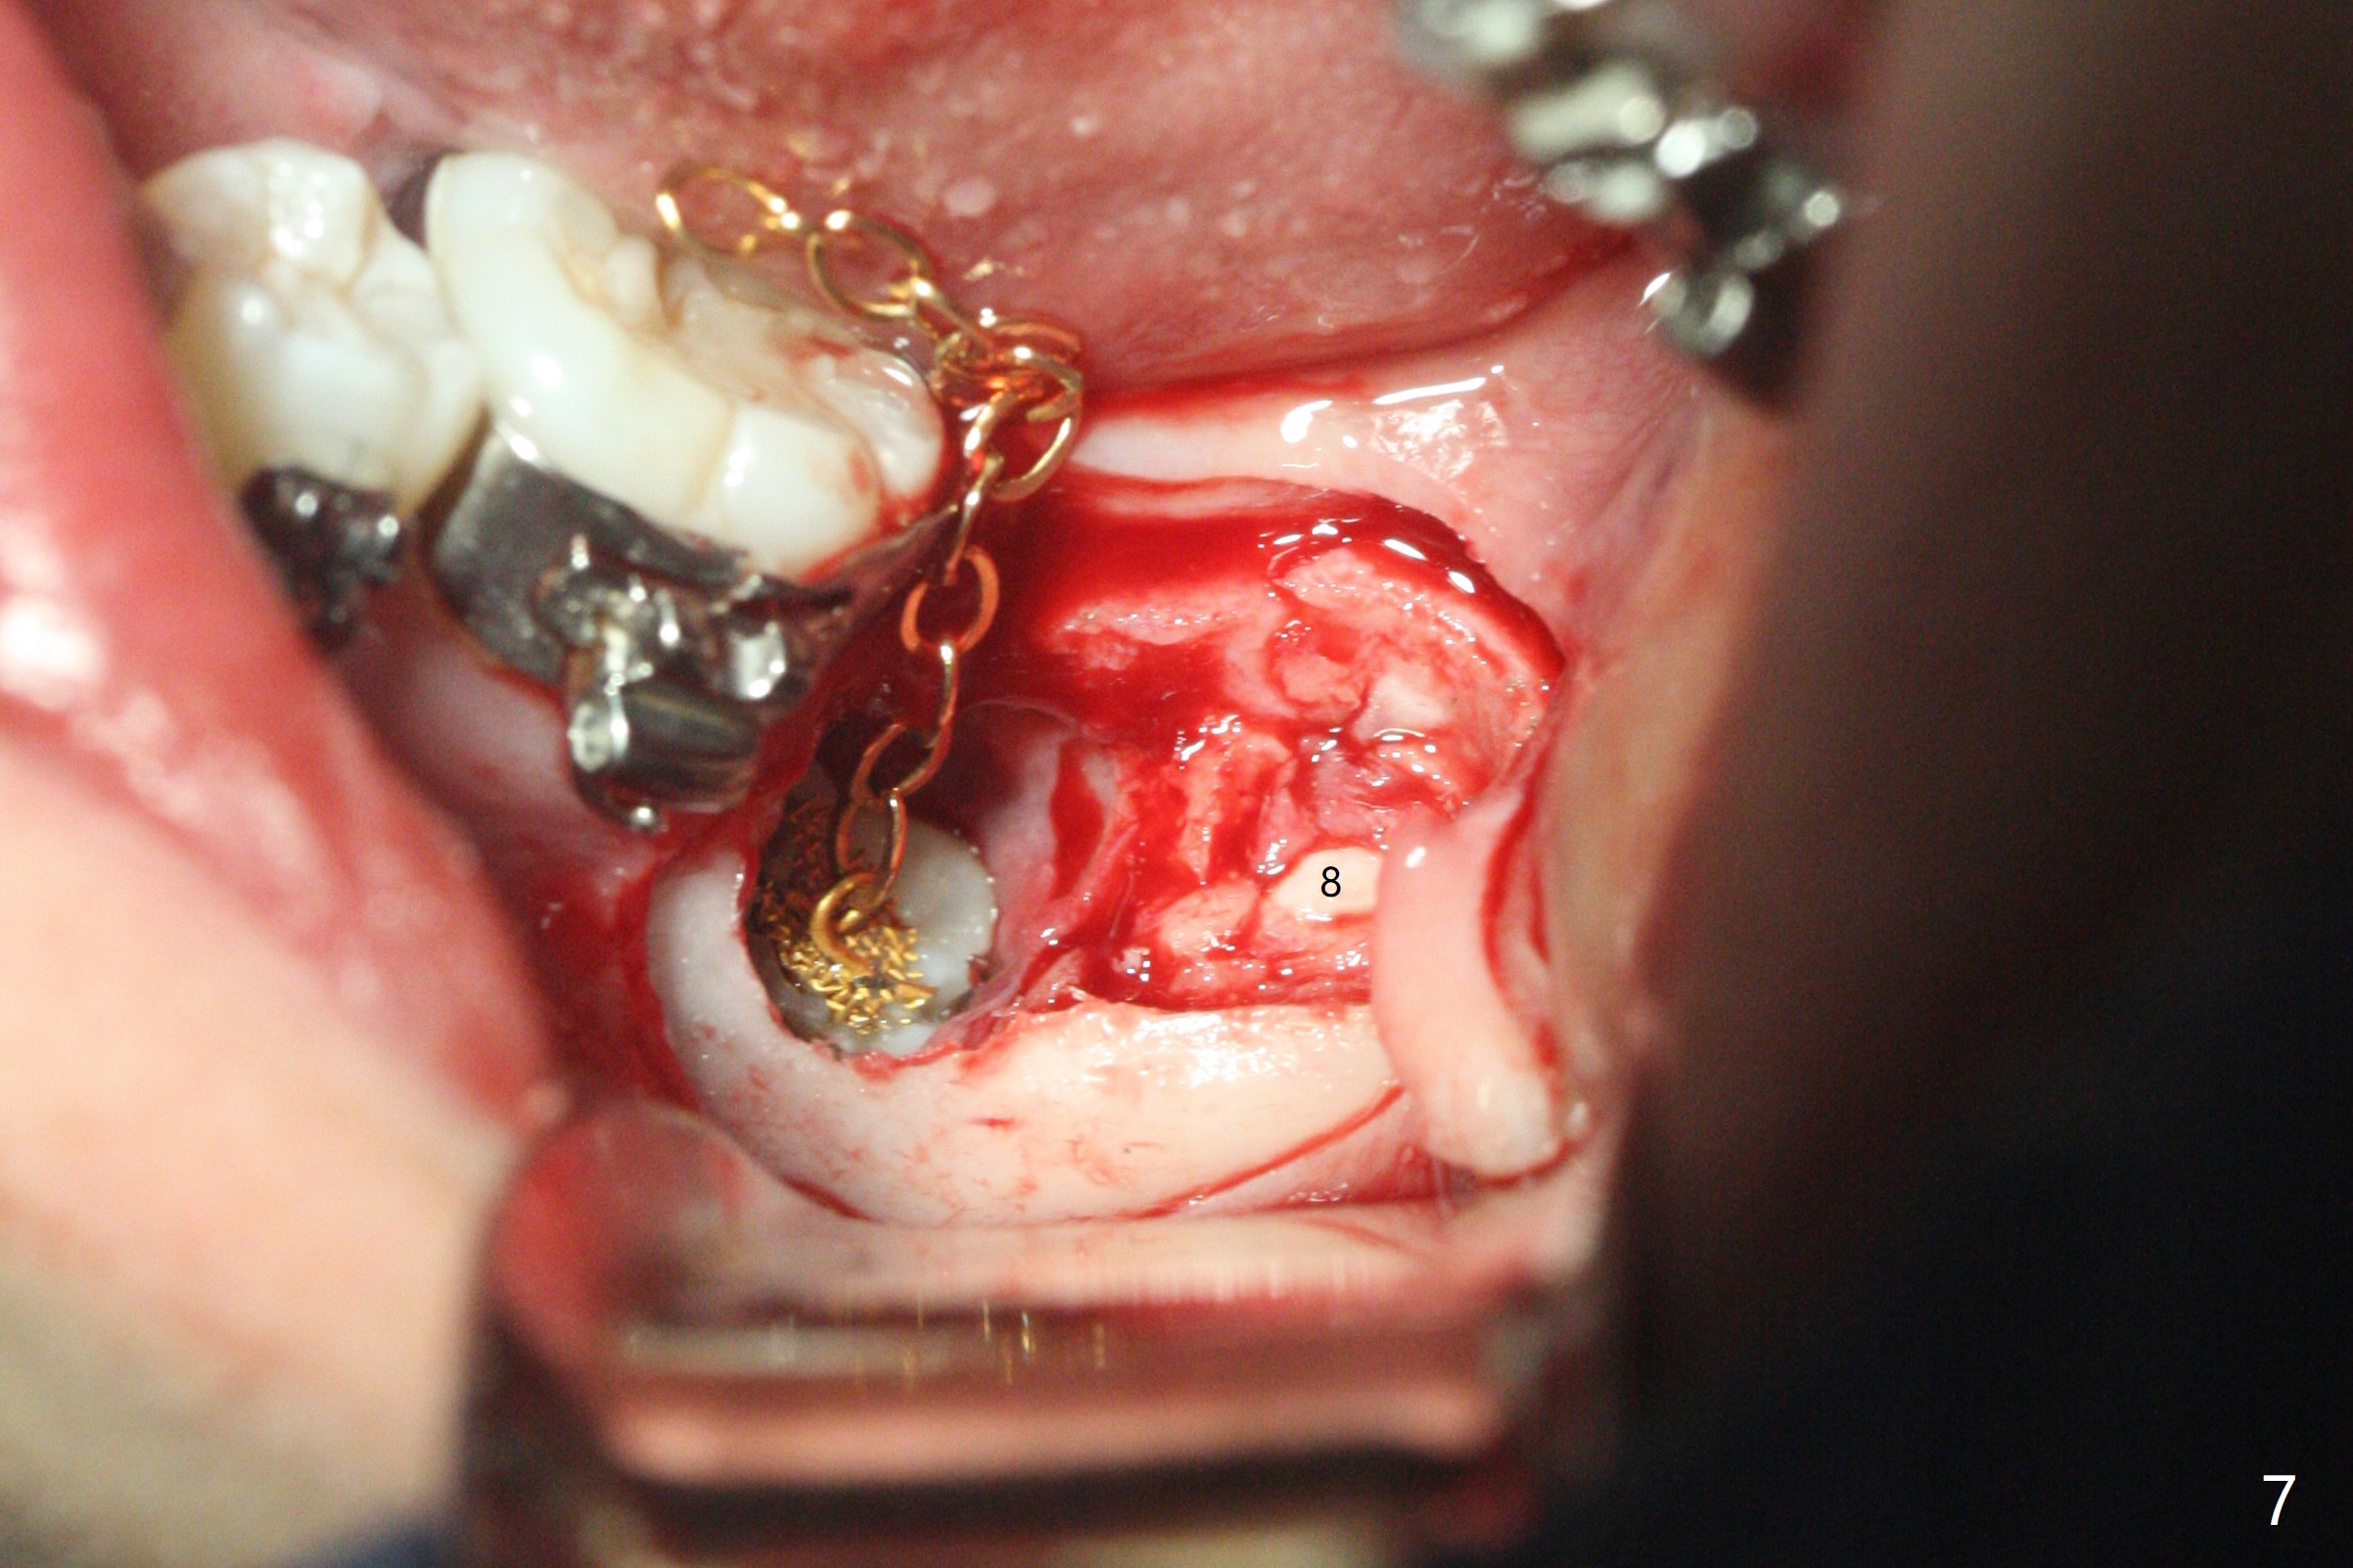

Treatment planning of surgical access to the impacted 7 (Fig.1) before CT analysis (to be canceled due to finance) include extraction of 8 (Fig.2) and removal of the bone coronal to 8 (Fig.3 red) so that there will be no bony block to 7 eruption (Fig.4). Place PRF or collagen plug in 8 socket to facilitate healing (Fig.3). Attach a retraction chain to the occlusal or buccal surface of 7 (Fig.6 pink) whenever it is convenient in term of hemorrhage and access (as mesial as possible). Remove 16 niti wires for brushing when the patient arrives. Cut 18 ss wire longer in the LL end (Fig.6 green to be bent to hook power chain (yellow)). Incision is shown as red in Fig.5. After 3 month delay, the thick buccal plate is removed from LL8 (1st) and 7 (2nd in sequence, as compared to Fig.2) to expose these unerupted teeth. In fact CT is not taken to decrease budget on the divorcing parents. A retraction chain is placed before extraction of LL8 with an intention to reduce hemorrhage (Fig.7). Although extraction requires several sectioning of the tooth, hemorrhage is mild to moderate. Instead of PRF and sticky bone (as compared to Fig.3), Osteogen plug is placed in the socket (Fig.8 OP). The bony septum between the 2 sockets is intentionally kept in place (*). 事实的确这样发生(图九:*)。埋伏牙不仅上移(^),而且远中移动(>),因为牵引方向(红虚线(橡皮筋),挂在上牙弓丝(图九:20ss:图十:18ss(之前))远端勾,积极牵引三个星期)。下次左上7放置舌侧纽扣,让病人更换橡皮筋。其实纽扣粘不住,上牙弓丝远中勾也不现实,只能使用橡皮筋挂在左上6,经常断。术后6个月,左下7继续上移(图十一)。这种低效率牵引仍然有效,牙齿继续上移,牙根长长(图十二:空箭头),但是受到左下6远中阻挡(*),所以下次在左上7咬合面装置舌侧纽扣和closed spring,改善牵拉方向(红箭头)。